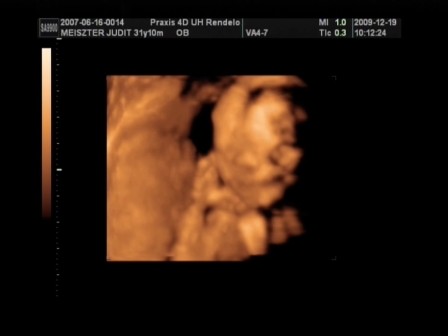

Minden rendben volt a 4D-n? Kislány vagy kisfiú?

nekem sajnos nem tudtak 4D-t készíteni, mert túl vastag volt a hasfalam! A lányokban már tudatosul, hogy testvérkéjük lesz?